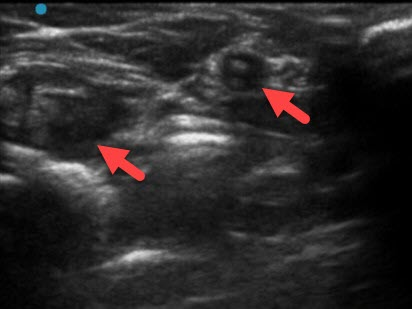

超声引导下腹股沟淋巴结穿刺注射

超声清晰可见淋巴结